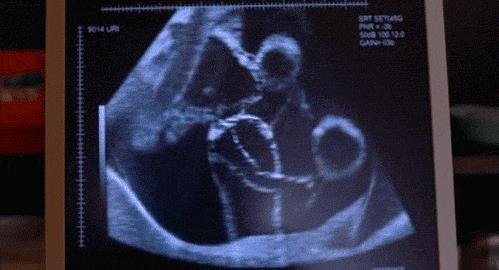

近日,已经孕38+3周的孕妇许女士在我院产检时被告知宝宝是臀位,这让想顺产的她担心不已。 经过医生综合评估后,为其实施了“胎位外倒转术”,成功将胎儿从臀位“倒转”到头位。

在充分的术前准备下,李勉勤主任通过术前B超、四步触诊,隔着肚皮,上推抬臀,下转胎头,按照胎儿适应的方向,缓慢推动,边操作边安抚着许女士,如“乾坤挪移”*法大**,胎儿由臀位顺利转变为头位, 整个操作过程用时2分钟左右,许女士也丝毫没有感到紧张与疼痛。目前,许女士已经出院在家待产。